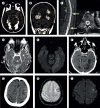

Findings: Between Dec 4, 2014, and Dec 4, 2016, 1410 patients were admitted to the hospital neurology service; 201 (14%) had symptoms consistent with arbovirus infection and sufficient samples for diagnostic testing and were included in the study. The median age was 48 years (IQR 34-60), and 106 (53%) were women. 148 (74%) of 201 patients had laboratory evidence of arboviral infection. 98 (49%) of them had a single viral infection (41 [20%] had Zika, 55 [27%] had chikungunya, and two [1%] had dengue infection), whereas 50 (25%) had evidence of dual infection, mostly with Zika and chikungunya viruses (46 [23%] patients). Patients positive for arbovirus infection presented with a broad range of CNS and peripheral nervous system (PNS) disease. Chikungunya infection was more often associated with CNS disease (26 [47%] of 55 patients with chikungunya infection vs six [15%] of 41 with Zika infection; p=0·0008), especially myelitis (12 [22%] patients). Zika infection was more often associated with PNS disease (26 [63%] of 41 patients with Zika infection vs nine [16%] of 55 with chikungunya infection; p≤0·0001), particularly Guillain-Barré syndrome (25 [61%] patients). Patients with Guillain-Barré syndrome who had Zika and chikungunya dual infection had more aggressive disease, requiring intensive care support and longer hospital stays, than those with mono-infection (median 24 days [IQR 20-30] vs 17 days [10-20]; p=0·0028). Eight (17%) of 46 patients with Zika and chikungunya dual infection had a stroke or transient ischaemic attack, compared with five (6%) of 96 patients with Zika or chikungunya mono-infection (p=0·047).

Interpretation: There is a wide and overlapping spectrum of neurological manifestations caused by Zika or chikungunya mono-infection and by dual infections. The possible increased risk of acute cerebrovascular disease in patients with dual infection merits further investigation.